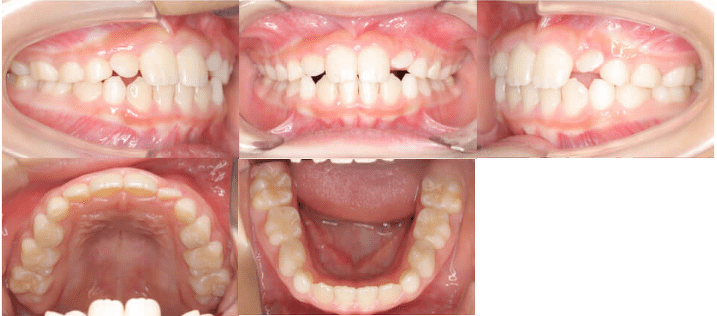

Before

患者さんは前歯の隙間が気になると来院されました。前歯の真ん中に隙間がある「正中離開」と前歯の噛み合わせが深い「過蓋咬合(かがいこうごう)」の症状がみられ、また前歯の間に隙間が空いていることで、前歯の脇のまだ永久歯が生えていない場所が狭くなっていました。

この症例では、マウスピース型矯正装置(インビザライン・薬機法対象外)で非抜歯の9ヵ月の矯正治療を行いました。前歯の隙間を閉じて永久歯の生えるスペースを確保し、前歯の重なりを小さくすることで噛み合わせが改善されました。矯正治療でスペースを開けたため、治療前にはまだ生えていなかった永久歯が正常な向きに伸びてきています。